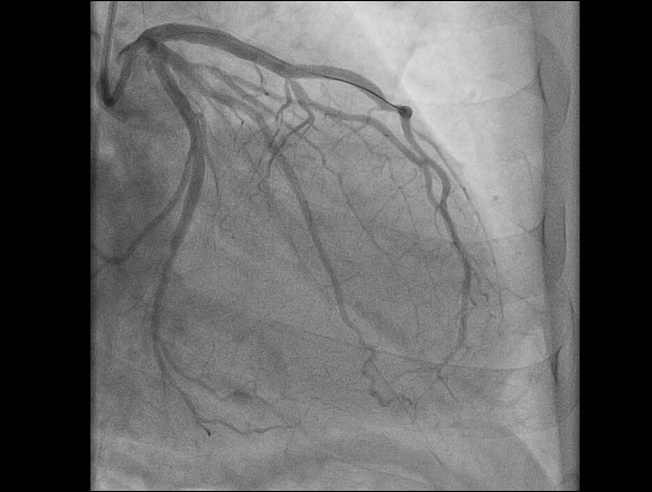

Недавний клинический случай балаковских медиков - яркий пример коварности сочетания физнагрузки и мороза: 59-летний мужчина почувствовал острую боль в груди во время уборки снега. Бригада "скорой" диагностировала "острый инфаркт миокарда" и немедленно начала лечение. Пациента доставили в сосудистый центр, где выявили тромботическую окклюзию передней межжелудочковой артерии* — сосуда, который в медицинской среде называют "артерией вдов" из-за высокого риска летального исхода при ее поражении. Операционная бригада балаковских медиков провела экстренное стентирование, полностью восстановив проходимость артерии.

После операции пациент прошел лечение в реанимационном и кардиологическом отделениях, в итоге он был выписан.